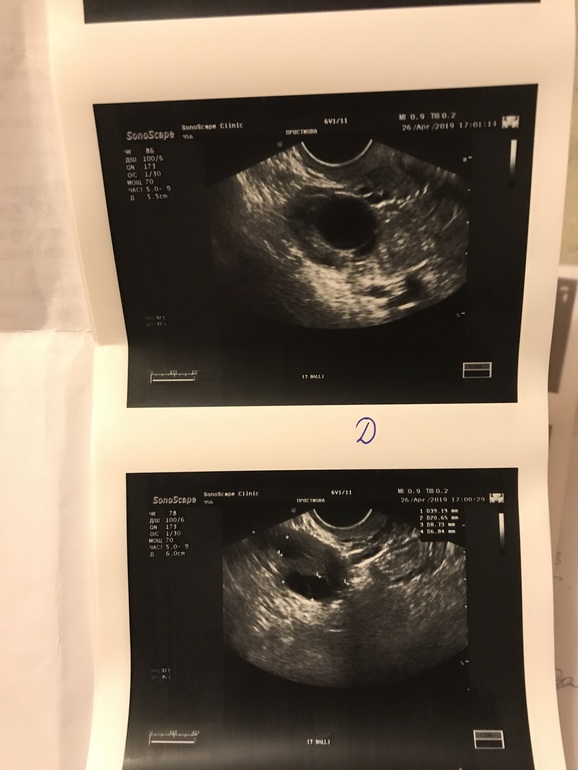

УЗИ на 12 и 19 дц - фоллики по 10-12 мм. Делаю тесты на О, на 28 и 29

ярчайшая полоска и 2 дня улыбается клеарблю, на 30 дц уже пошёл спад по тестам, по ощущениям на 29 дц ныл живот, как перед мес, немного похожее ощущение.

На 33 дц иду на узи, в надежде на желтое тело 😁💛Но там только ДФ разглядели 18*15. Я подумала может перепутали и это все же ЖТ, но по форме не похоже... как думаете, шта это вообще такое?) Был всплеск лг, но ДФ не лопнул? И что теперь, куда он денется? Когда ждать мес?Я конечно попробую через неделю ещё сходить посмотреть, что там происходит, но все же интересно. И кстати жидкость была в Пмп, но мало, 4 мл, не было овуляции скорее всего ☹️